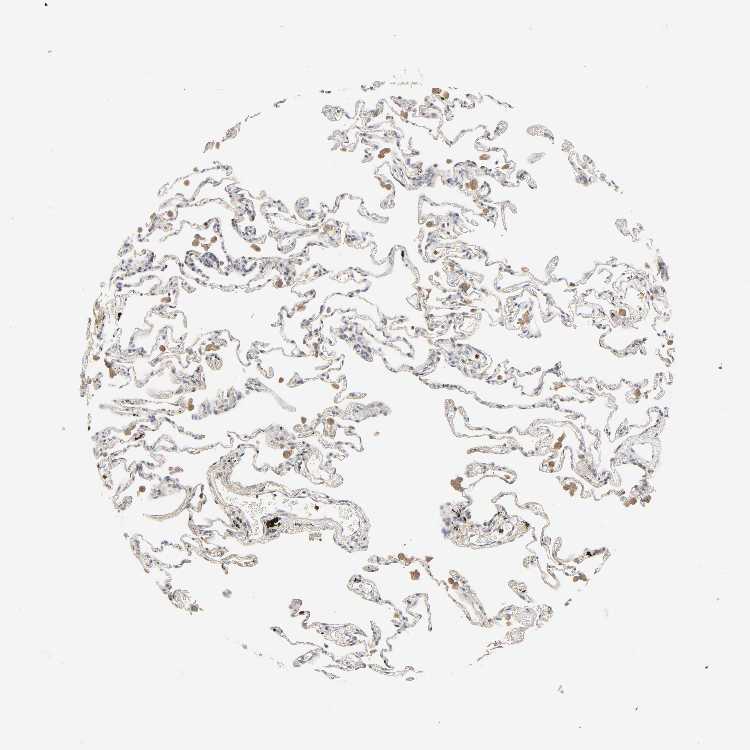

LUNG - Antibody stainingi

Antibody staining in the annotated cell types in the current human tissue is reported as not detected, low, medium, or high, based on conventional immunohistochemistry profiling in selected tissues. This score is based on the combination of the staining intensity and fraction of stained cells.

Each image is clickable and will lead to virtual microscopy that enables deeper exploration of all samples and also displays staining intensity scores, fraction scores and subcellular localization as well as patient and tissue information for each sample.

Antibody HPA000962Antibody HPA004119

Alveolar cells Not detected-

Alveolar cells type I -Not detected

Alveolar cells type II -Not detected

Endothelial cells -Not detected

Macrophages Not detectedMedium